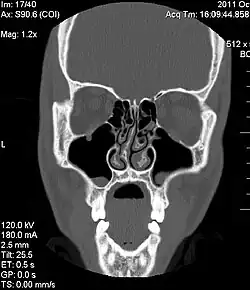

O desvio de septo nasal é a causa mais comum de obstrução nasal.[7] Uma história de trauma no nariz é frequentemente presente, incluindo trauma do processo de nascimento ou microfraturas.[7] Um profissional médico, como um otorrinolaringologista (médico dos ouvidos, nariz e garganta), tipicamente faz o diagnóstico depois de tirar uma história detalhada do paciente e performar um exame físico.[7] Exames de imagem do nariz às vezes são usados para auxílio diagnóstico.[7]